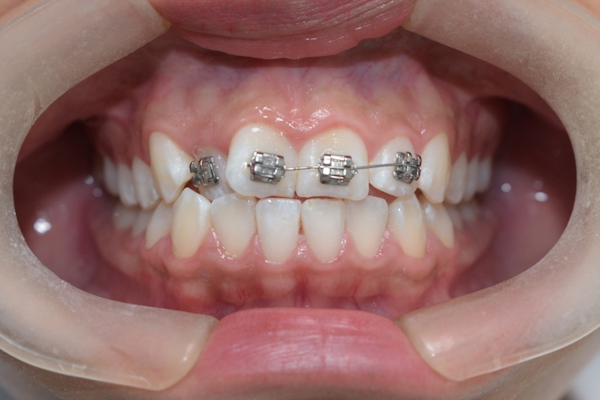

Caso de corrección de apiñamiento con ortodoncia fija

Paciente femenino de 13 años de edad, acude a consulta por dientes desalineados en la zona frontal, buscando mejorar la estética de su sonrisa y facilitar la higiene dental.

Se colocó ortodoncia fija con brackets metálicos, iniciando la fase de alineación y nivelación. El tratamiento incluye arco ortodóncico para corrección progresiva, ligadura metálica para control de movimientos dentales, y ajustes periódicos para guiar la posición dental.

La paciente en fase inicial de tratamiento

En la evaluación clínica se observaron:

- Apiñamiento anterior superior

- Rotaciones dentales en incisivos laterales

- Desalineación en el sector estético (zona visible al sonreír)

- Relación oclusal susceptible de mejora